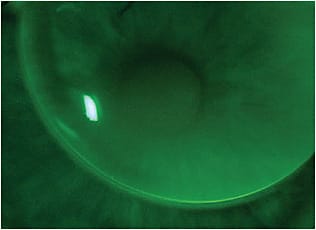

- Focus on the fit. Many GP multifocal lens designs have a specific fitting process. Make sure to understand the ideal on-eye placement to maximize success. Some lenses are meant to sit a little higher on the eye (Figure 1), while others are meant to stay more centered during lens wear. A little bit of movement is necessary, but patients will most often have difficulties if GP lenses move too much.

Figure 1. This slightly “lid-attached” high-riding GP fit may be ideal for some lens designs. - Look for ways to maximize surface hydration. Depending on the lens design, know your options for lens material and for treatments that will improve the surface wetting of the lens.